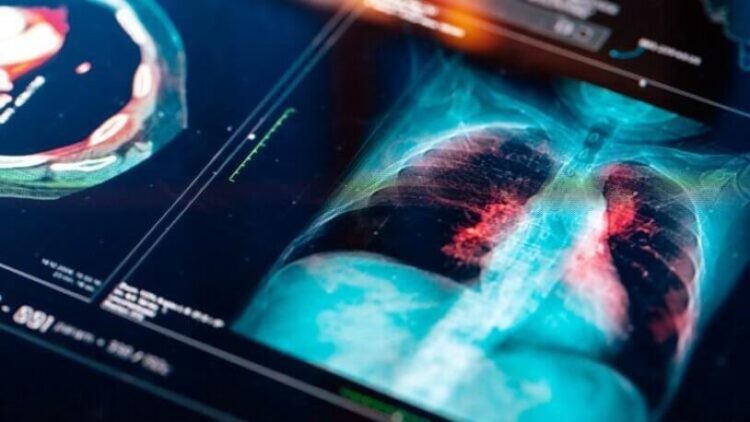

Bir türlü iyileşemeyince Brogan Williams Haziran 2021’de yeniden doktora gitti ve onkoloğu boynunda bir yumru keşfedince tarama ve biyopsi yapıldı. Bilgisayarlı tomografi taraması da yapılan Williams’ın akciğerlerinde kanser ve sıvı teşhis edildi.

Bu yılın haziran ayında onkoloğa giden Brogan’ın boynunda bir yumru fark edince doktoru onu acil tarama ve biyopsiye yönlendirdi. 18 Temmuz’da çekilen tomografi sonrası akciğerlerinde kanser ve sıvı olduğu sonucuna varıldı.

Brogan, kanserin çok geç fark edildiğini söylüyor ve ekliyor: “Aslında ilk başta göğsümü tarasalardı, o noktada ciğerlerimde kanser olduğunu görürlerdi. Şimdi her iki akciğerde ve çok ilerlemiş durumda. Meme kanserini yendikten bu kadar kısa bir süre sonra kanserin geri döneceğini düşünemediler.”

Konuyu örneklerle de açıklayan Okutur, “Örneğin öksürük, akciğer kanserinin en sık görülen belirtisidir. Covid-19 pandemisi esnasında öksürüğü olan ve Covid-19 enfeksiyonu geçirdiğini düşünerek doktora gitmekten korkan, evde kalmaya devam eden, bu yüzden de teşhisi geciken birçok akciğer kanseri vakası bulunmaktadır. Benzer şekilde koku kaybı bazı beyin tümörlerinde de görülebilmektedir. Halsizlik, iştahsızlık ve kilo kaybı da kanser olgularının çoğunda görülen ortak belirtilerdir” ifadelerine yer veriyor.

Bu durumun özellikle akciğer kanseri için geçerli olduğunun altını çizen Okutur, “Öksürük şikâyeti üzerine yapılan akciğer görüntülemesindeki bulgulara bakılarak Covid-19 enfeksiyonu düşünülen ve Covid-19 tedavisi verilerek evde karantinaya alınan, ancak daha sonra durumun düzelmemesi üzerine yapılan ileri tetkiklerde mevcut belirti ve bulguların akciğer kanserinden kaynaklandığı saptanan, hatta bu nedenle hayatını kaybeden hastalar bildirilmiştir” diyor.